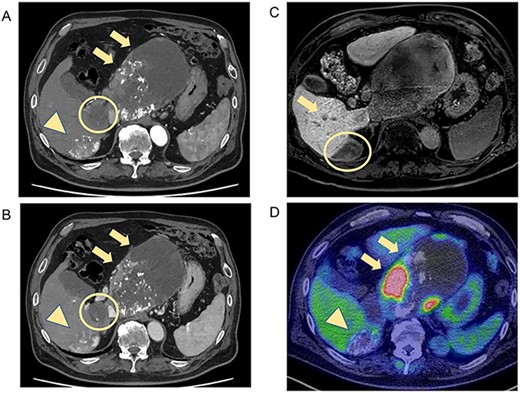

Postoperatively, tumor marker concentrations were normalized promptly after surgery (Fig. 4). The patient is currently alive at 12 months postoperatively without recurrence.

Treatment timeline with the pre- and postoperative serum AFP and PIVKA-II concentrations.